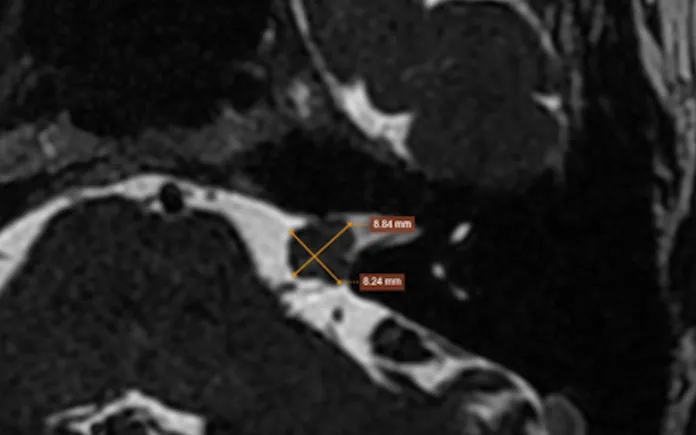

Hình ảnh chụp cộng hưởng từ của bệnh nhân phát hiện khối u góc cầu tiểu não - lỗ tai trong trái dọc theo đường đi của dây thần kinh số 8.

Bác sĩ tiếp tục chỉ định bệnh nhân chụp cộng hưởng từ (MRI) sọ não tìm căn nguyên gây bệnh, hình ảnh phát hiện khối vùng góc cầu tiểu não - lỗ tai trong trái dọc theo đường đi của dây thần kinh số 8, kích thước khoảng 9x4mm. Sau khi hội chẩn kỹ lưỡng, bác sĩ kết luận nguyên nhân chính xác gây tình trạng ù tai, nghe kém của bệnh nhân do khối u tại dây thần kinh số 8 gây ra.